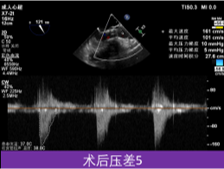

植入后超声评估:

超声评估血流动力学改善明显